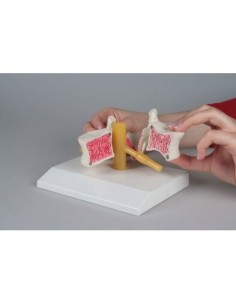

Colonne lombaire 3B Scientifique avec hernie discale dorsolatérale A76/5